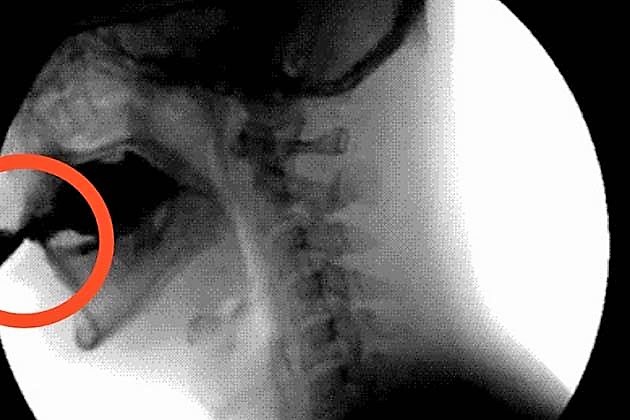

Quando a euforia finalmente passa, vem a hipoglicemia. Você se sente irritado e lento. Você perdeu toda a água contida na bebida de cola. E com ela se foram todos os nutrientes tão importantes para o bom funcionamento do seu corpo. Nutrientes que poderiam ter hidratado o seu corpo ou fortalecido os seus dentes e ossos. E para piorar, as chances de você desenvolver diabetes e ter de usar uma bomba de insulina como a da foto aumentam.